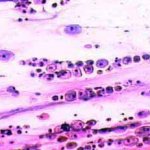

Πινακοθήκη κυτταρολογικών ευρημάτων ΙΙΙ

Οι πινακοθήκες κυτταρολογικών ευρημάτων, έχουν σαν στόχο να εμπλουτίσουν την κυτταρολογική εμπειρία σπουδαστών και ειδικευομένων, όπως ένας άτλαντας.

Παρουησιάζονται λοιπόν τυχαία ευρήματα, από το καθημερινό γυναικολογικό ιατρείο.